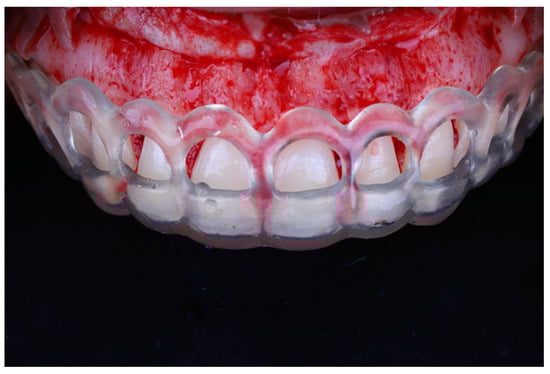

A full thickness mucoperiosteal flap was elevated past the mucogingival junction (Figure 7). The surgical guide was then placed again to determine the extent of osteoectomy needed (Figure 8), and the bone was marked with a round carbide bur. Using an end cutting carbide bur, osteoectomy was then performed; osteoplasty was performed after to remove buccal bone buttressing (Figure 9). The guide was then placed for a final check before internal vertical mattress sutures were placed using a monofilament non-resorbable material (5.0 Prolyne, Ethicon Inc, Somerville, NJ, USA) and hemostasis was ensured.

Figure 7.

Mucoperiosteal flap elevated.

Figure 8.

Surgical guide placed to determine level of osteoectomy.